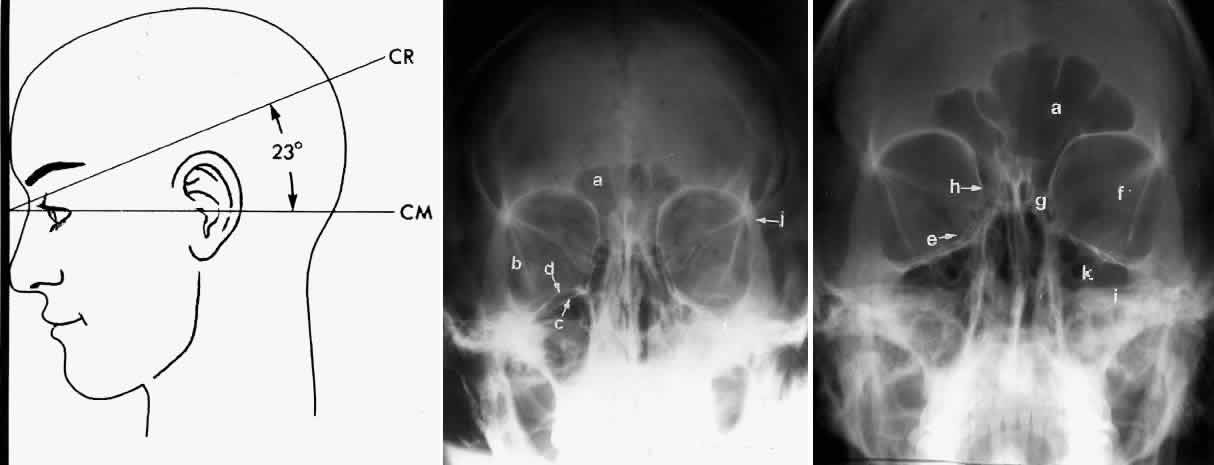

WATERS PROJECTION

In an attempt to improve the visualization of the maxillary and ethmoid sinuses, in 1915 Waters and Waldron7 described a radiographic projection (Fig. 2) that eliminated the overlapping shadows of the dense petrous ridge of the temporal bone. Waters projection is created by placing the chin of the patient on the x-ray cassette with the canthomeatal line (the line that connects the lateral canthus and the external auditory meatus) at 37 degrees to 45 degrees.5,6 This orientation is accomplished if the nose of the patient is approximately 0.5 to 1.5 cm above the x-ray plate.7,8 A mnemonic is—the patient raises the chin up to sip water.

Fig. 2. A. Schematic showing positioning for a Waters projection. (CM, canthomeatal line; CR, central ray) B. Radiograph of a Waters projection. The petrous ridge lies below the maxillary sinus. (a, frontal sinus; b, medial orbital wall; c, innominate line; d, inferior orbital rim; e, orbital floor; f, maxillary antrum; g, superior orbital fissure; h, zygomatic-frontal suture; i, zygomatic arch) (A; Rao VM, Gonzalez CF: Plain film radiography and polytomography of the orbit. In Gonzalez CF, Becker MH, Flanagan JC [eds]: Diagnostic Imaging in Ophthalmology, pp 1–7. New York, Springer Verlag, 1986)

Waters view provides the best image of the maxillary antrum and good images of the orbital rim, orbital floor, zygomatic bones and arches, lesser wing of the sphenoid, and infraorbital foramen. This view is useful to the clinician in orbital floor fracture assessment because of the clear image of the orbital floor and the underlying maxillary sinus. The floor of the orbit should form a continuous radiographic line with the lateral wall of the orbit. Confusion can occur regarding the location of the orbital floor and its relationship to the orbital rim. The orbital floor is located inferior to the orbital rim not in the same plane, because of the orientation of the patient's head in Waters projection. A soft tissue density in the roof of the maxillary sinus or opacification of the floor of the sinus suggests an orbital floor disruption.